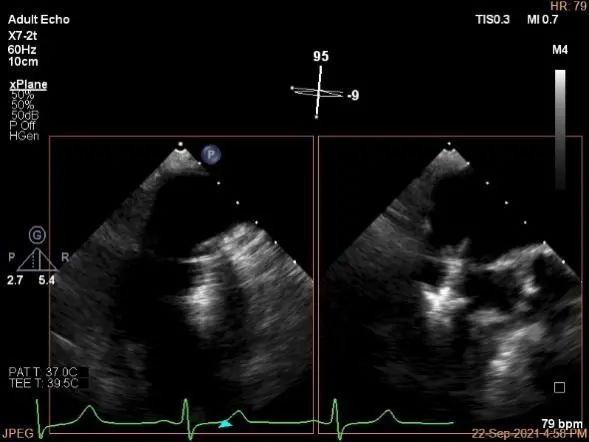

3D:P1区脱垂并腱索断裂,部分AC受累,Width:11.4mm

3D-color:重度MR,4级